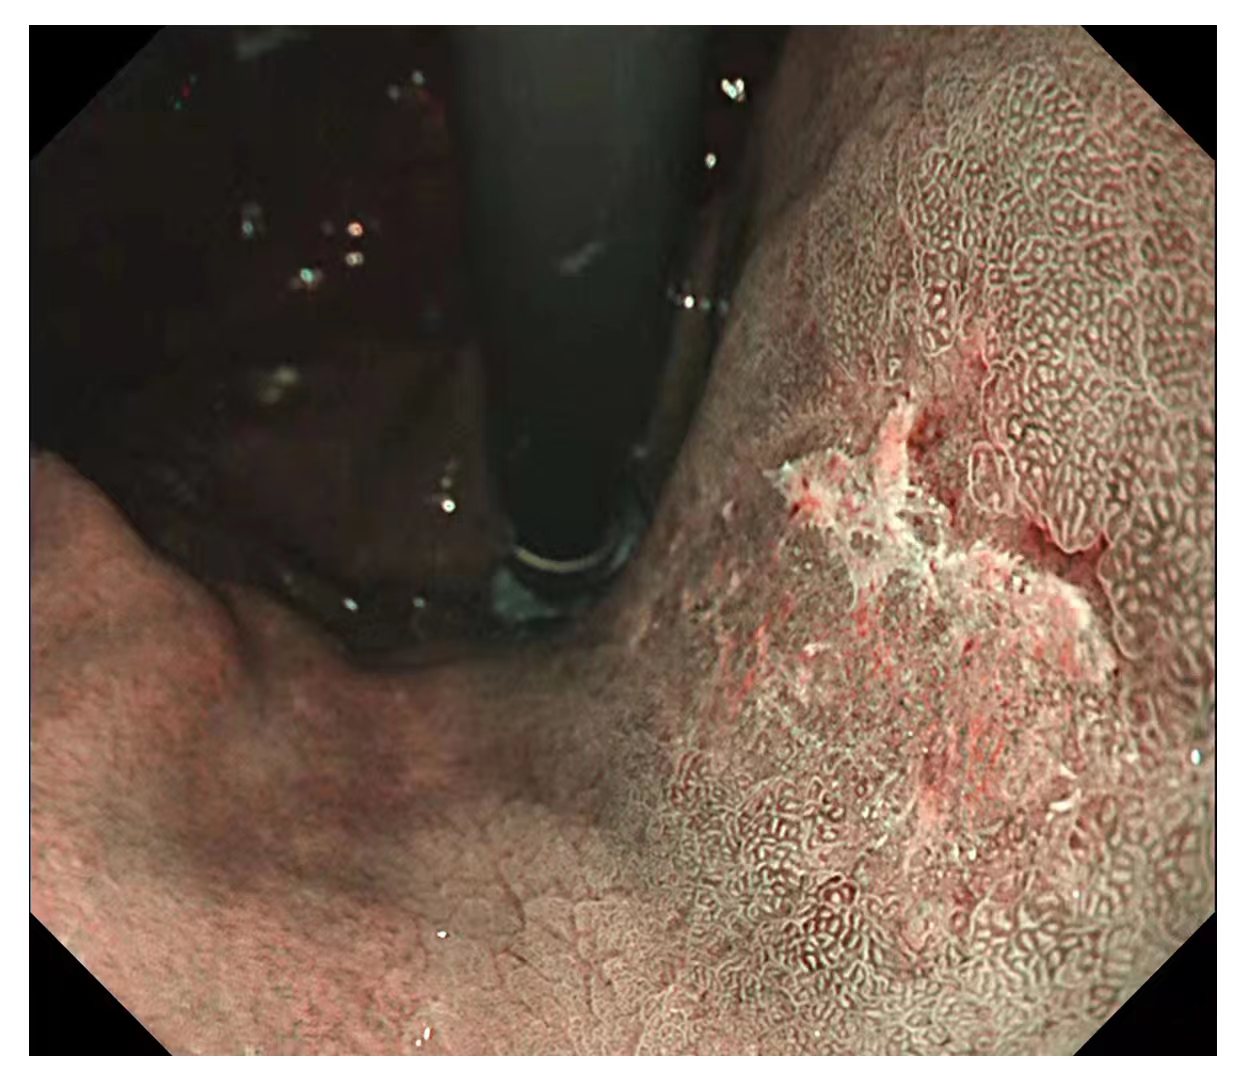

内镜中心在胃镜检查、结肠镜检查、息肉治疗、取除异物、超声内镜检查和食管支架术、内镜下黏膜剥离术等方面开展了大量的工作,结肠的回肠末端到达率98%,结肠息肉检出率达35%,早癌检出率1.5%。

图片可能引起轻度不适,请谨慎查看

内镜中心独立完成了多例食管、胃、结肠早癌完整切除术,并成功开展了食管良性狭窄切开术,间质瘤挖除术,食管癌伴食管狭窄支架置入术,消化道异物取出术,痔疮Ⅱ度以内的硬化术等。

内镜中心人员,在积极开展内镜检查治疗的同时学习病理知识。通过学习和分析病理图片,和病理科的老师共同交流,进一步观察消化道早癌显微镜下的病理变化,对消化道早癌有了更全面、更深刻的认识。